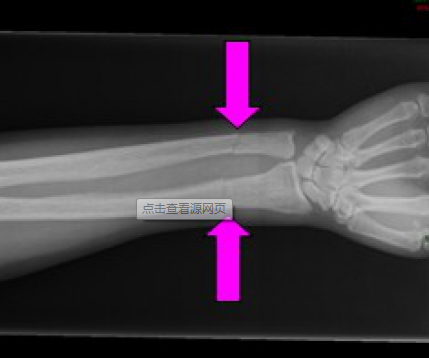

骨质疏松骨折示意图

骨质疏松骨折的特点及治疗难点

1. 骨质疏松骨折患者卧床制动后骨丢失加快,骨质疏松会加重;

2. 骨折多为粉碎性,难以获得满意的固定;

3. 内固定易松动,植骨易被吸收;

4. 骨折愈合时间长,易发生延迟愈合、不愈合;

5. 再骨折风险大;

6. 多为老年人,常合并多脏器疾病,全身状况差;

7. 致残率、致死率较高,严重影响生活质量和寿命。